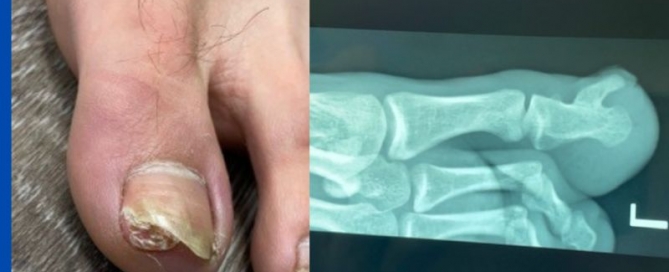

Subungual exostosis

Blog's main page I see a regular amount of subungual exostosis throughout the year. Typically they have been treated as ingrown toenails (IGTN) first. The GP and the podiatrist may [...]